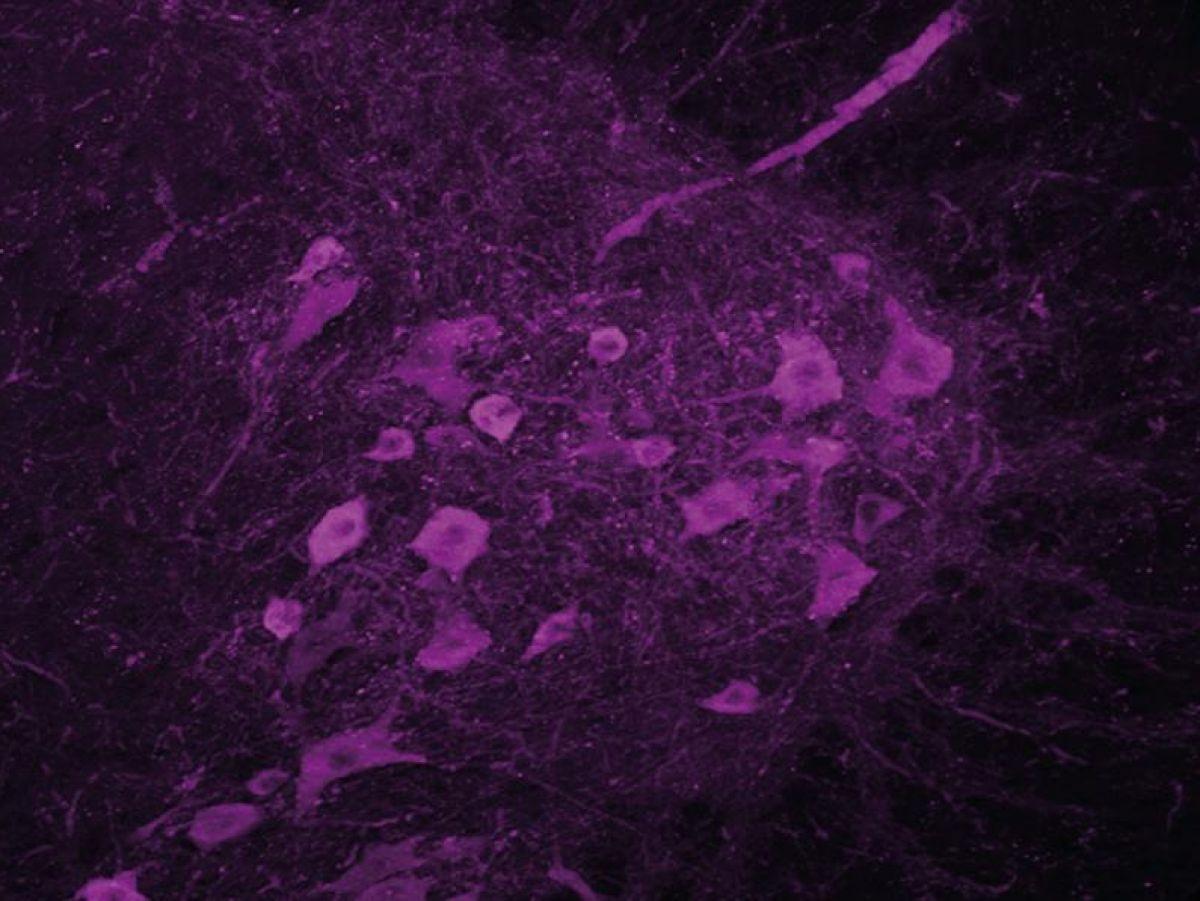

Il existe deux types de neurones moteurs (ou motoneurones): les neurones moteurs centraux, situés dans le cortex moteur, qui envoient les ordres de contraction à la moelle épinière, et les neurones moteurs périphériques, qui transmettent ces commandes aux muscles. Chez un patient atteint de la SLA, les deux dégénèrent, ce qui coupe la communication entre le cerveau et les muscles. Non sollicités, ces derniers ne se contractent plus et finissent par s’atrophier.

« C’est pour cela que nous nous sommes intéressés à l’hypothalamus, qui est la structure du cerveau en charge de la régulation de notre poids. Nous avons observé que les neurones exprimant l’orexine et la melanin-concentrating hormone (MCH), molécules qui régulent la prise alimentaire mais aussi l’activité et le sommeil, étaient altérés chez les personnes atteintes de SLA, raconte le chercheur. Naturellement, s’il y a des troubles de l’expression de ces neurotransmetteurs dans le cerveau, il y a sûrement aussi des problèmes de sommeil. »

Les souris traitées récupèrent un meilleur sommeil, et leur motoneurone est préservé. »Les motoneurones lombaires semblent ne plus mourir. Ils sont bien là, mais on ne sait pas s’ils sont encore fonctionnels. »